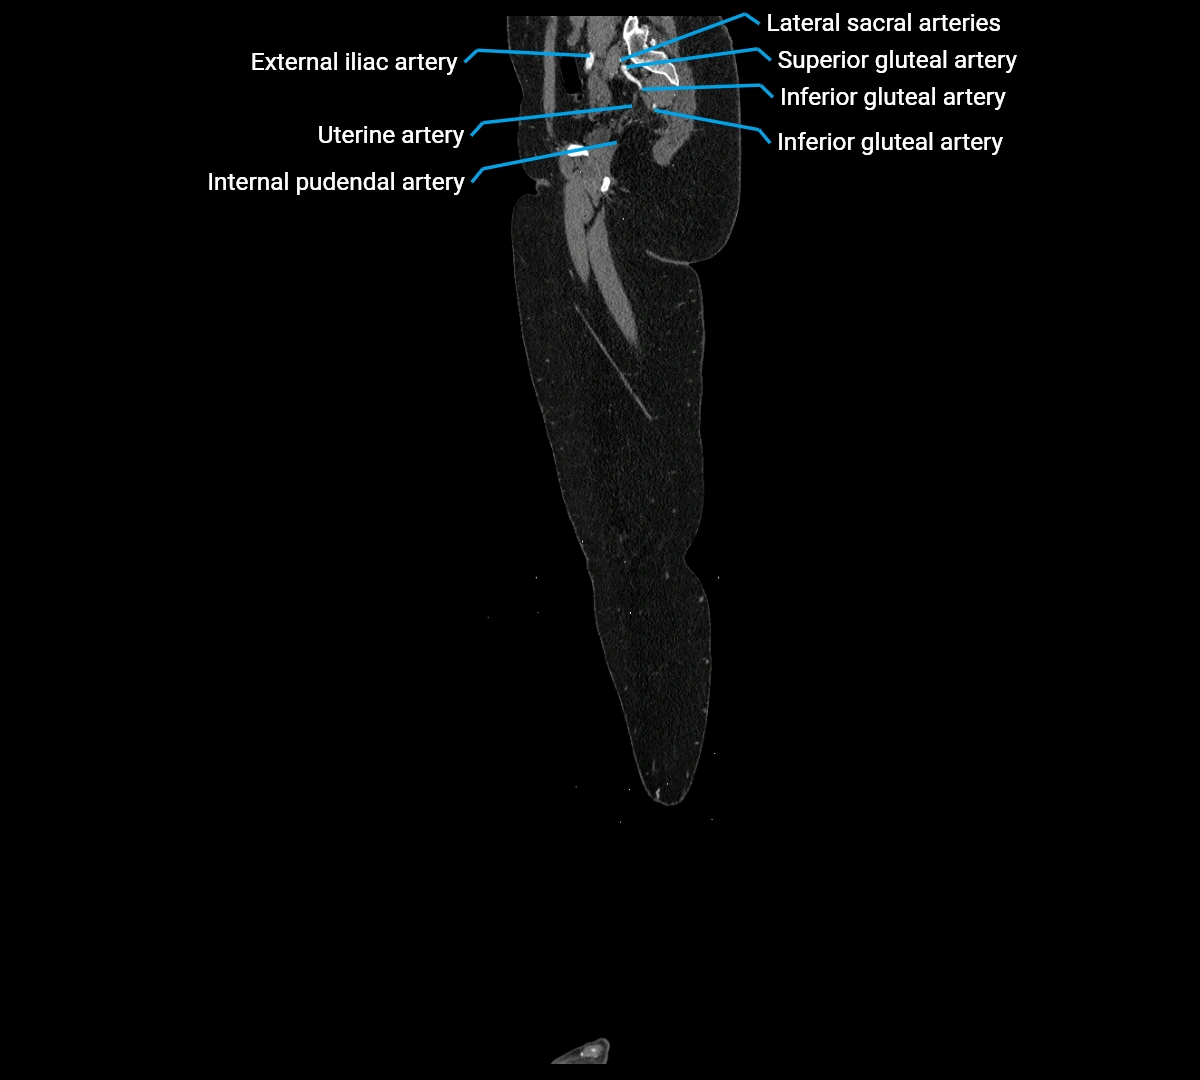

Contrast-enhanced CT (CTA):

• Gold standard for abdominal aortic imaging

• Provides excellent detail of lumen, wall, aneurysm, thrombus, and branch vessels

• Multiplanar and 3D reconstructions help in aneurysm measurement, stent graft planning, and dissection evaluation